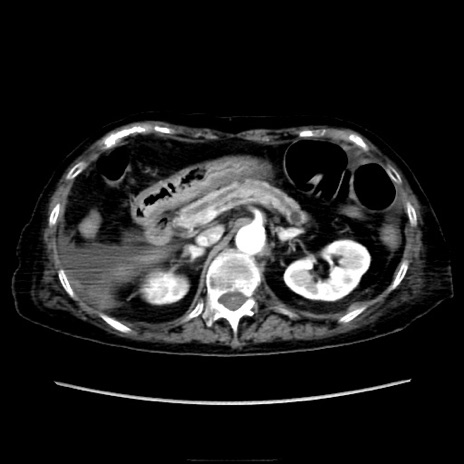

症例40(横断像)

【症例】90歳代女性

【主訴】腹痛・嘔吐

【現病歴】 食欲低下、嘔吐があり昨日他院受診。肺炎と診断され入院となる。入院後より腹部全体に圧痛あり。胃管留置され経過みていたが、症状持続するため、

当院転院となる。

【既往歴】胸椎圧迫骨折、胆石症

【身体所見】腹部:中央に激痛あり、圧痛あり、反跳痛不明

【データ】WBC 17100、CRP 18.82

横断像